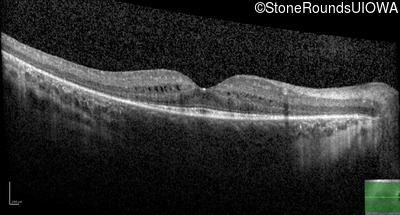

Age at visit: 8 years

OD OS

This 8 year old girl first had trouble trick-or-treating at age 4.